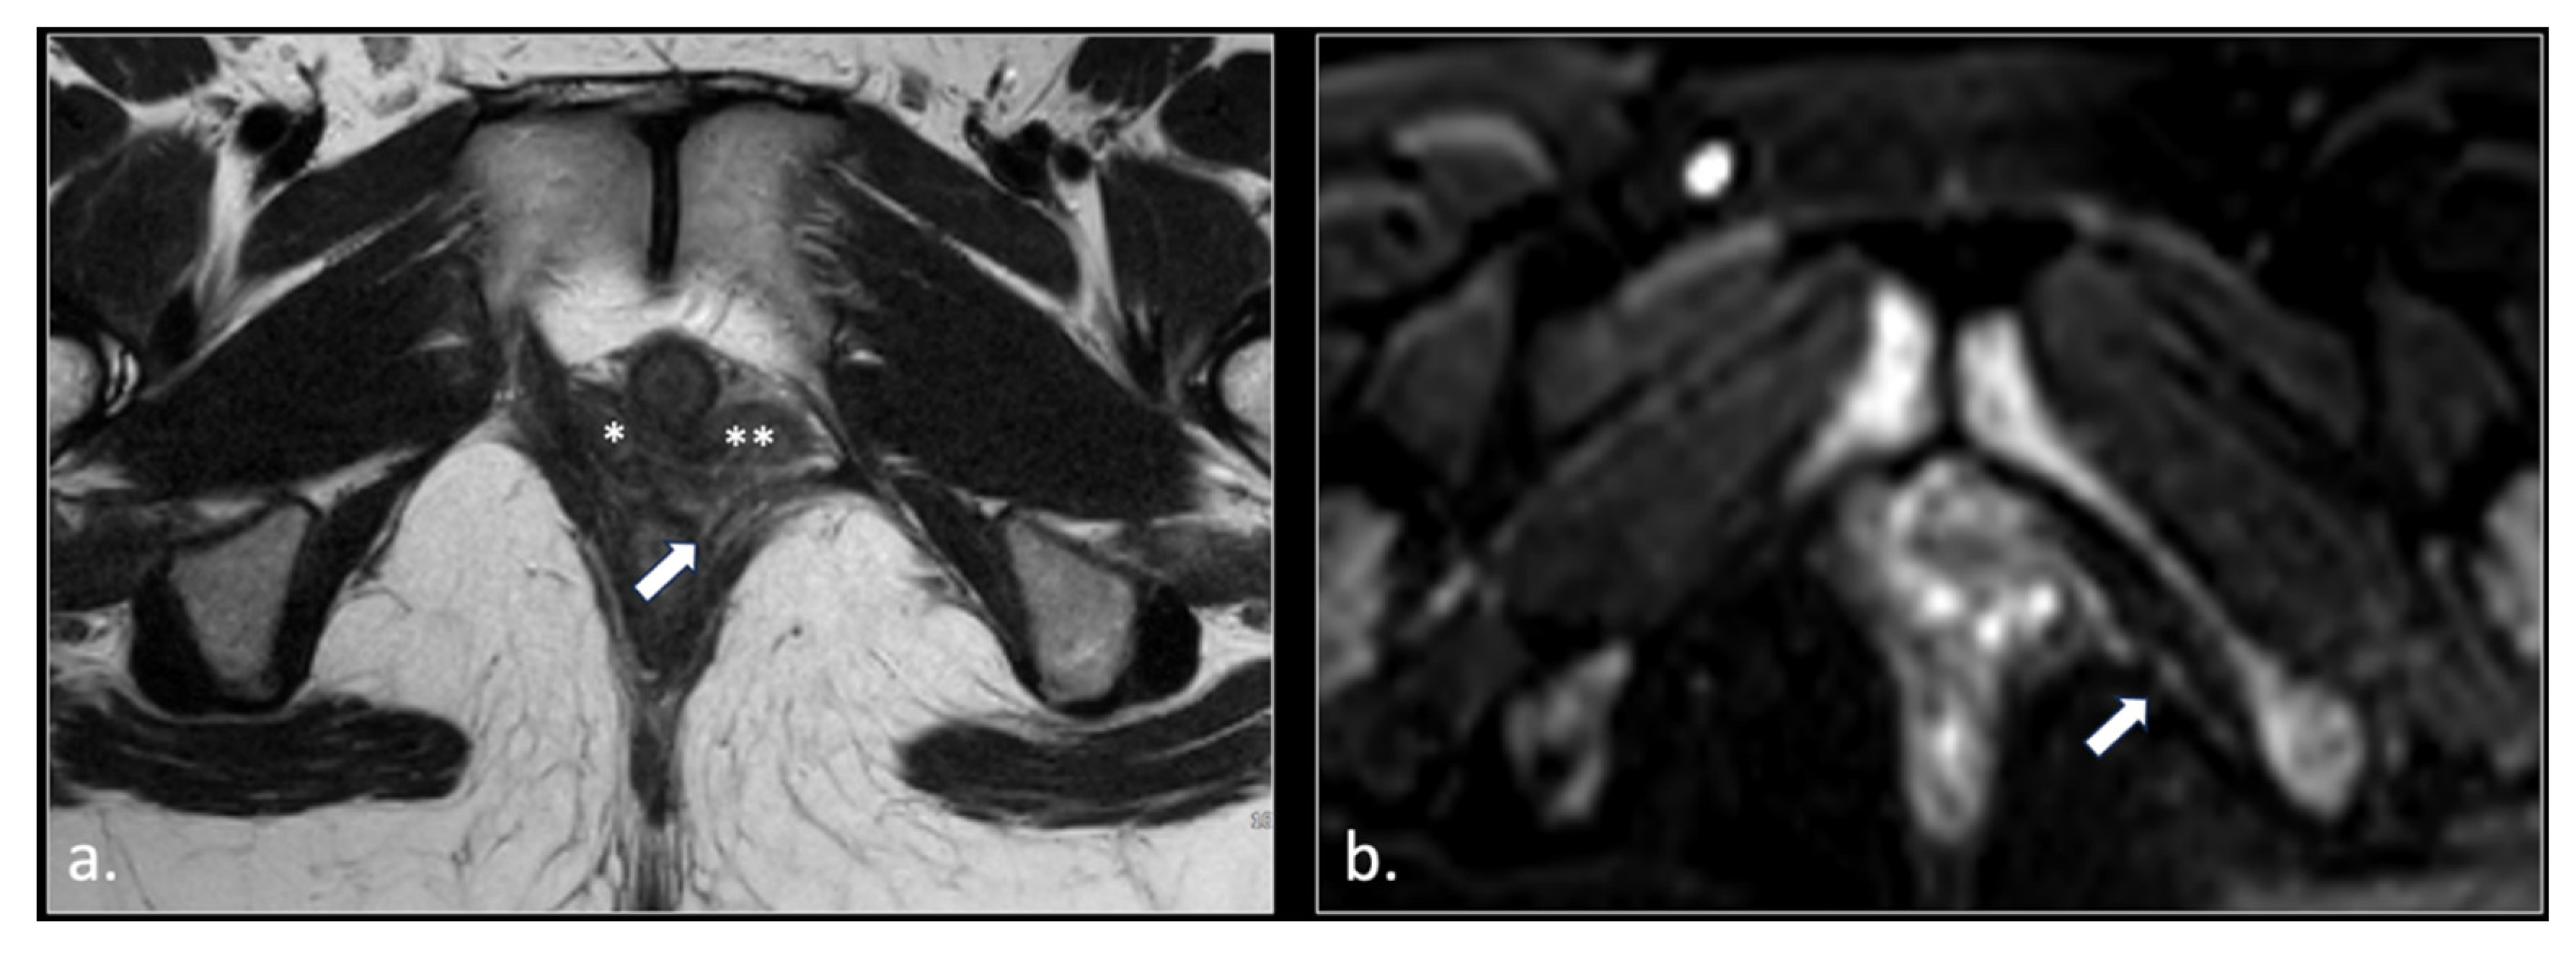

Figure 3.

37-year-old male with pudendal neuralgia. Axial T2-weighted scan through mid-pelvis shows hypertrophy of the left piriformis muscle. Roots of the lumbo sacral plexus lies on the anterior surface of the muscle. On the other hand, S2 and S3 roots of the pudendal plexus (arrow) can be seen along the medial surface of the muscle within an incomplete canal created by the two bellies (* and **) of the muscle.

Figure 6.

43-years-old female with chronic post-traumatic pudendalgia. (a) Axial T2-weighted scan shows a normal right side pubo-coccygeus muscle (*). On the left side, an avulsion of the pubo-coccygeus muscle can be seen. The residual left pubo-coccygeus muscle is thinned (arrow). The vagina in shifted on the left side (**). (b) Axial b600 DWI scan demonstrates diffuse hyperintensity of the left pudendal nerve (arrow).